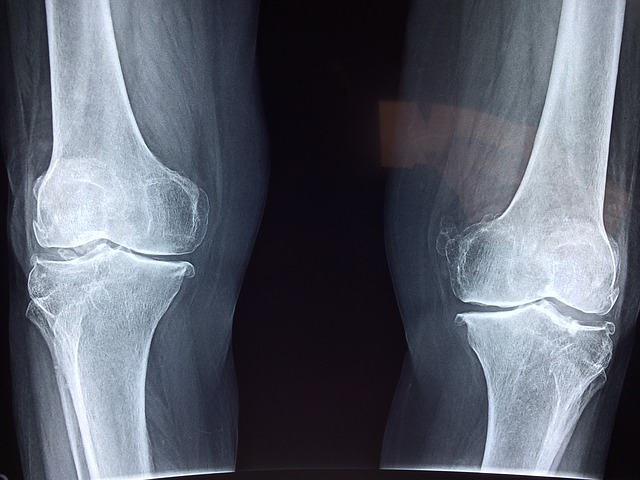

For some of us, the thought of walking up a staircase or climbing into a car gives us a shudder- as we think about the pain in our knees that’s likely to follow. Osteoarthritis in the knees, that painful feeling we experience in our knee joints, is an all too common occurrence these days, and it’s also the reason that hundreds of thousands of knee replacements are performed each year. There’s some confusion as to why the incidence of this condition has significantly increased over the years- is it the higher prevalence of obesity, inflammation, other environmental factors? The jury is still out but new research offers some possibilities. For further understanding, take a look Here. And even if osteoarthritis is not your worry, there are plenty of other causes of pain and problems in your knees as you get older. For a good overview of the mechanics of the knee and what can go wrong, gently take a seat and Click Here.